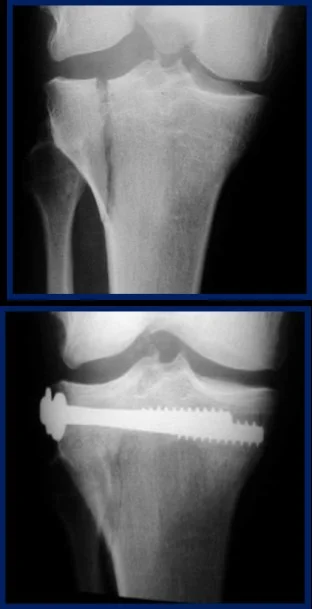

| Screws | Good fixation – stable – Can apply good inter‑fragmentary compression In simple fractures Can be applied percutaneous | ![]() ![]() |

| Plates and Screws | Metaphyseal fractures Diaphyseal fractures Pelvis | ![]() |